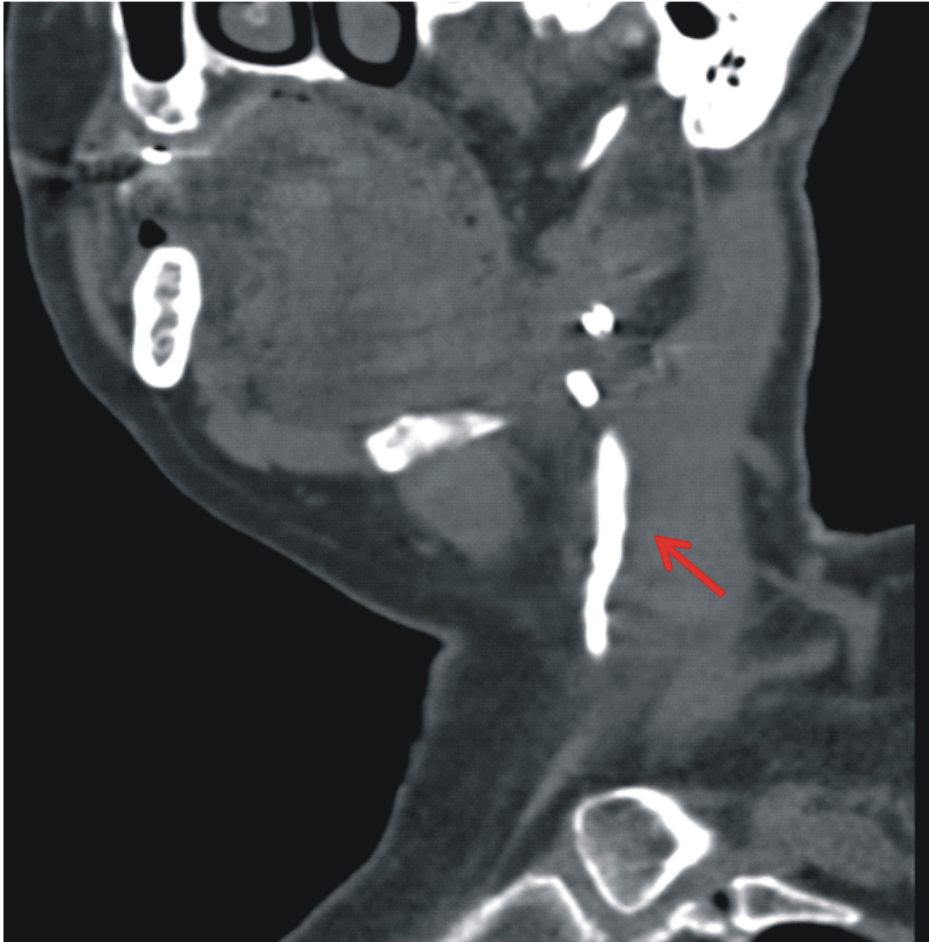

Была выполнена мультиспиральная компьютерная томография с фистулографией: контрастное вещество заполняет неправильной формы неравномерной ширины свищевой ход размером до 10´5,5 мм, протяженностью до 4,5 см, доходящий до левой поднижнечелюстной слюнной железы. Воспаление левой поднижнечелюстной слюнной железы (рис. 2).

Рис. 2. МСКТ мягких тканей шеи с фистулографией. Стрелкой указан свищевой ход, заполненный контрастным веществом